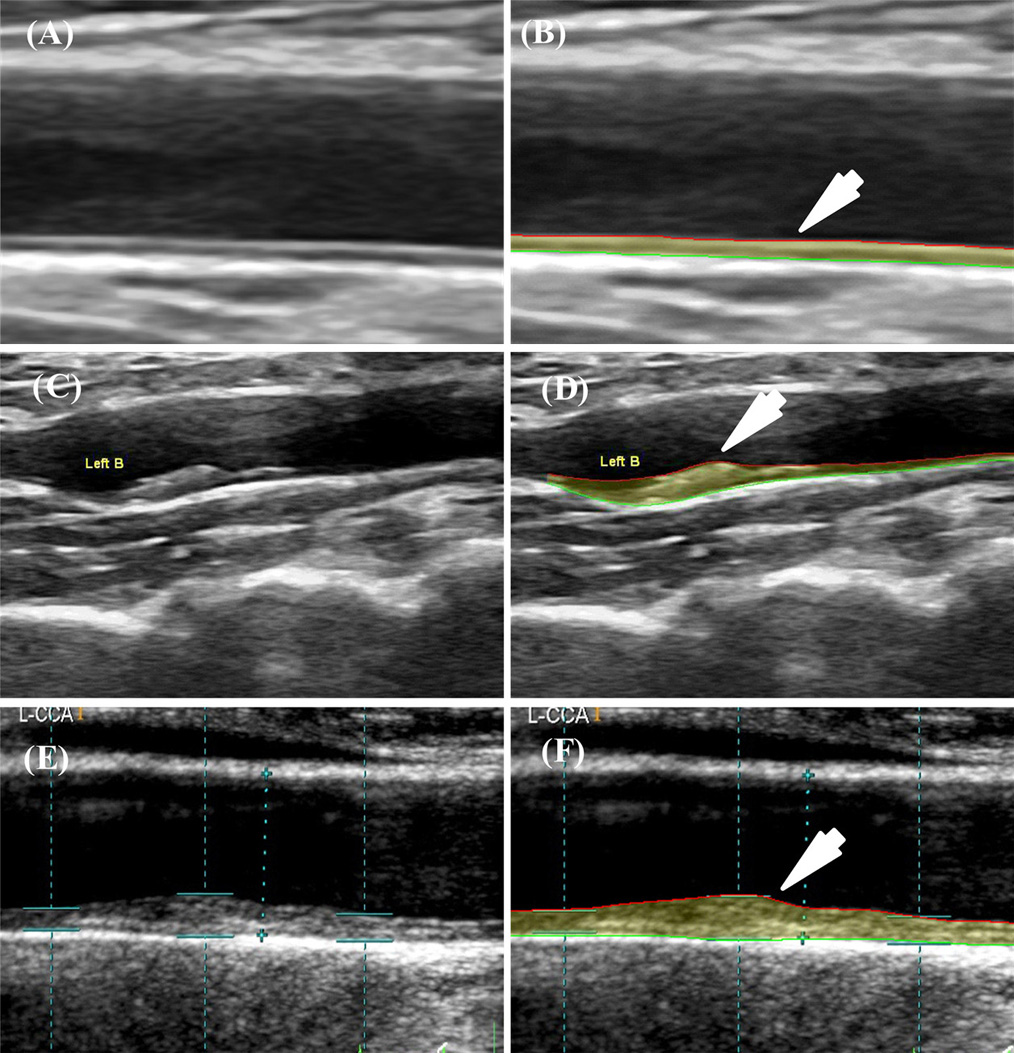

Figure 7 shows the screening of atherosclerotic patients suffering from DM using AECRS1.0 risk calculator. AECRS1.0 used the CUSIP consisting of five phenotypes: IMTavg, IMTmax, IMTmin, IMTV and TPA for risk stratification. AECRS1.010yr used the CUSIP such as IMTave10yr, IMTmax10yr, IMTmin10yr, IMTV10yr and TPA10yr corresponding to 10-year CVD risk prediction. Here, the suffix “10yr” indicates the 10-year prediction of the CUSIP. Figure 7 shows a sample of three patients classified based on the composite risk score (blood biomarker and image-based phenotypes), using the AECRS1.0. It was observed that the low-risk patient (Row 1) had smaller IMTavg (0.65 mm) and high-risk patient (Row 3) have comparatively higher IMTavg (1.55 mm). Our study hypothesizes that high-risk and moderate-risk patients can benefit from preventive screening before clinical manifestations.

Figure 7Risk stratification based on AECRScurrent and AECRS10yr. Row 1: Patient 798 (low risk): (A) Original Image (B) Image processed using AtheroEdge・2.0; CUS: IMTavg=0.65 mm, IMTmax=0.71 mm, IMTmin=0.57 mm, IMTV=0.04 mm, TPA=11.95 mm2, AECRS1.0curr=14%; IMTave10yr=0.74 mm, IMTmax10yr=0.80 mm, IMTmin10yr=0.66 mm, IMTV10yr=0.06 mm, TPA10yr=13.11 mm2, and AECRS1.010yr=17%; HbA1C=5.9%. Refer Appendix B for more samples.Row 2: Patient 1726L (low-moderate risk): (A) Original Image (B) Image processed using AtheroEdge・2.0; CUS: IMTave=1.15 mm, IMTmax=2.23 mm, IMTmin=0.48 mm, IMTV=0.62 mm, TPA=39.02 mm2, AECRS1.0curr=50%; CUS10year: IMTave10yr=1.29 mm, IMTmax10yr=2.37 mm, IMTmin10yr=0.62 mm, IMTV10yr=0.76 mm, TPA10yr=40.7 mm2, and AECRS1.010yr=57%; HbA1C=8.3%. Row 3: Patient 11L (low-of-high risk): (A) Original image (B) Image processed using AtheroEdge・2.0; CUS: IMTavg=1.55 mm, IMTmax=2.39 mm, IMTmin=1.08 mm, IMTV=0.38 mm, TPA=51.69 mm2, AECRS1.0curr=65%; CUS10year: IMTave10yr=1.69 mm, IMTmax10yr=2.53 mm, IMTmin10yr=1.22 mm, IMTV10yr=0.41 mm, TPA10yr=54.23 mm2, and AECRS1.010yr=69%; HbA1C=7.9%. (Courtesy AtheroPoint, Roseville, USA)